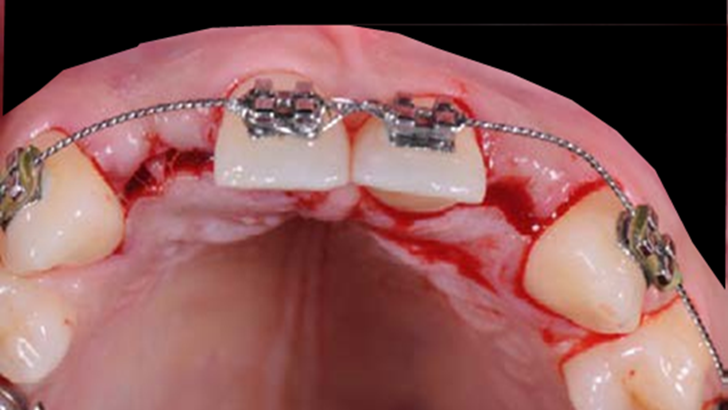

Clinical case: Patient-centered approach: treatment strategy for Root Membrane Technique & delayed implant placement

- Courtesy of Dr. Yoshiharu Hayashi, Japan -

Socket Shield Technique, anterior esthetics, maxillary anterior, esthetic, esthetics, delayed implant placement, socket preservation, AnyRidge, Root Membrane Kit, Root Membrane Technique, Partial Extraction Therapy, PET, esthetic zone, fuse abutment, Dr. Yoshiharu Hayashi,#11,#21,#22